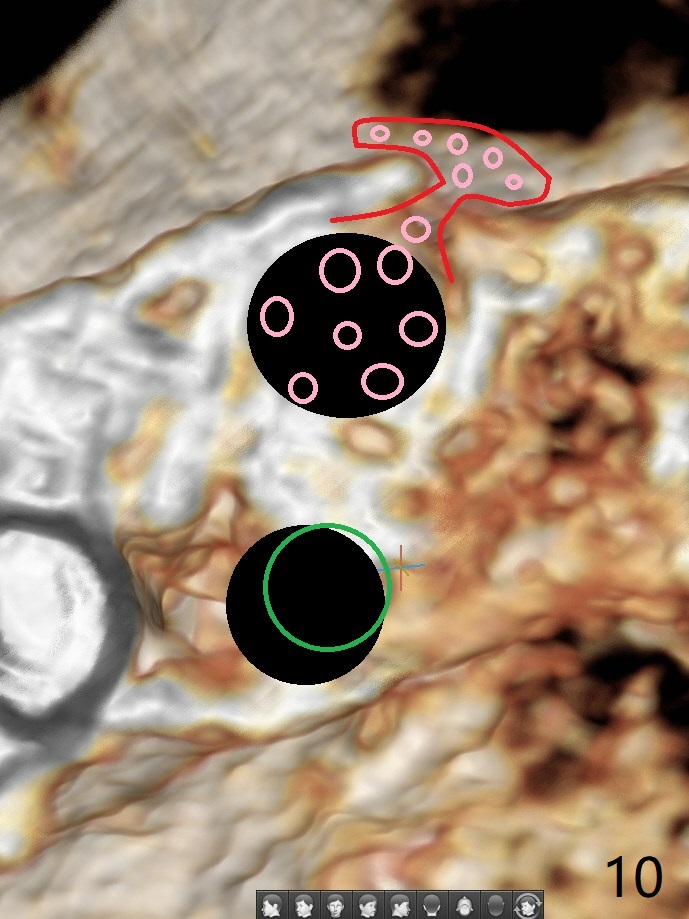

52岁女左上4颊侧牙龈显著肿胀(图一:*(颊侧骨板缺失))伴有瘘道(<),拔除前,在3植牙牙冠切缘舌侧形成开口(图二:*,准备纠正基台不全就位(<);4初步钻洞不正。改变钻头方向后(图三),完成植体放置(图四),并且安置修复基台(4.5x4(2))。磨去3牙冠近中面(图六:*),牙冠和基台反时针旋转(图六:弯箭头),基台完全就位(图四:箭头),调𬌗后,制作4临时牙冠(图六),放置后者前,覆盖半张PRF膜(促进下面粘性骨粉愈合)。图五,六颊侧隆起是因为下面放置许多粘性骨粉。图七是术前CT3D图像(冠状切面),显示颊侧(B),腭侧(P)牙根。拔牙后显示中隔(图八:S),植体植入腭侧窝(图九:绿色),四面骨质包绕,包括中隔;为了修复颊侧骨板,首先放置半张PRF膜(红色)紧贴颊侧骨板腭侧/牙龈,防止骨粉从瘘道流失,然后放置粘性骨粉(图十:粉红色)。术后2.5月3颊侧牙龈仍然红肿(图十一,十二:*),可能与基台袖太短有关(2毫米,图二至四),所以更换袖3毫米的基台(图十三)。术后四个月(牙冠粘固)3颊侧牙龈炎症明显减退(资料没有显示)。术后2.5月4颊侧骨板没有塌陷(图十二,与术后即刻对比(图六))。3基台放置太颊侧,所以在牙冠腭侧制作小的开口(图十四:>),让多余粘固剂流出。取模前3螺丝就拧紧(35Ncm),而4由于有大的开口,粘固后才拧紧(30Ncm)。两个邻牙其中一个可以取出,容易去除另外一个牙冠残余粘固剂。